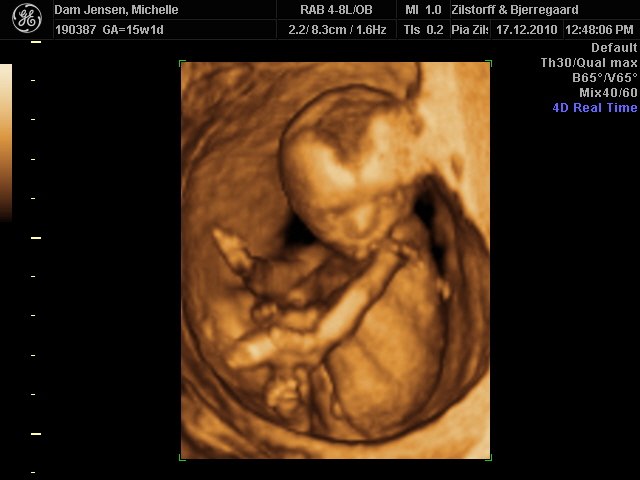

Det var så fantastisk at se hende i 3D selvom jeg ikke var længere henne end 15+1

men vægt mæssigt er hun 15+3 hehe så hun spiser godt må man sige

Alt var perfekt, hjerter, nyre, kranie tarme osv.. så vi var super stolte og glade